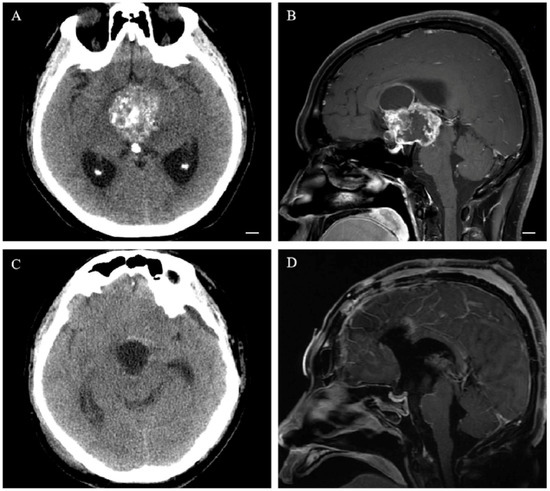

2.3. Neuroradiological Evaluation

3.2. Neuroradiological Features